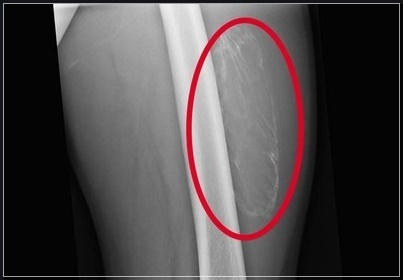

골화

골화는 세포에 의해 석회침착이 일어나는 것으로 관절이 움직이지 않는 것 같은 증상입니다. 이 증상은 보통 아침에 심하고, 섬유 근육통의 가장 초기 증상 중 하나입니다.

오랫동안 앉아있거나 누워있었다면, 몸과 관절이 같이 반응하지 않게 되고 기온이 변하거나 습도가 달라질 때 이런 증상이 나타납니다.